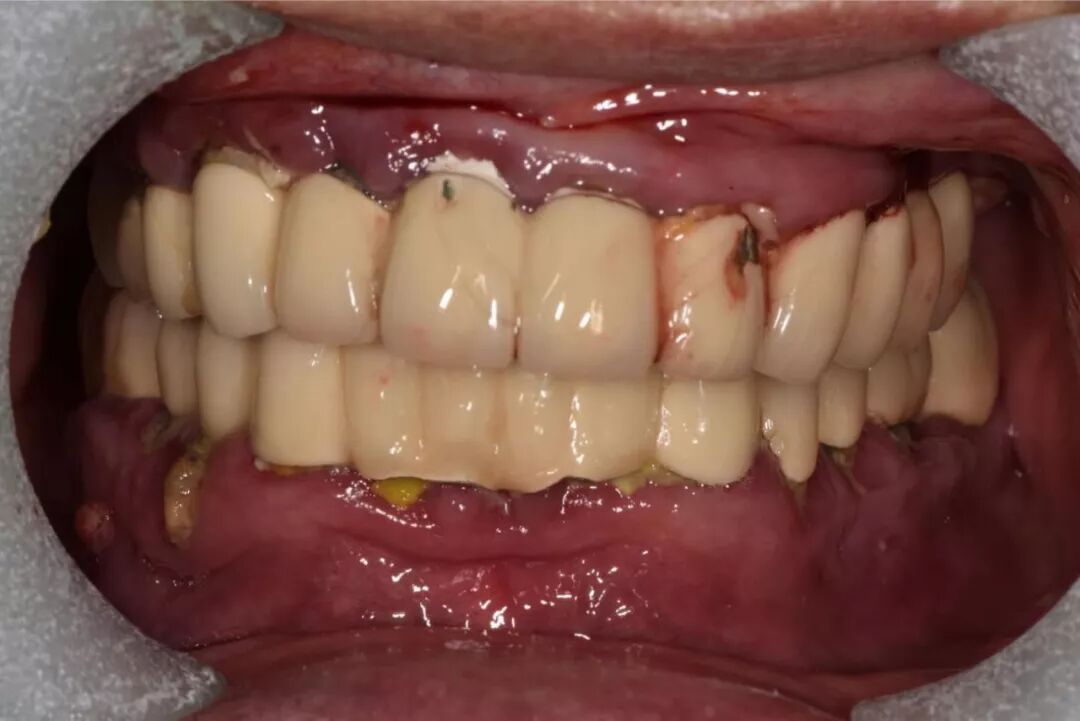

另外,烤瓷桥中的极品——“长江大桥”现象,则是普遍存在于中国各城市各基层牙科的不规范现象,与普通烤瓷桥不同,其本质是一种违反口腔生物力学原理的设计,其最常见的转归是全口牙报废,临床上很多先在基层做,两三年后去医院拆,对口腔健康的影响令人咂舌。

这样的病例实在太多,公立医院和部分高端民营口腔机构每年都要拆除很多例,后续治疗则费时费事费钱费脑筋,而且此类患者来源于社会各阶层,我见过的病例包括一些同事医生(非牙医)的父母,医生的健康意识不代表其家人,而你无法想象其中一例是拥有几百亿资产的企业家,医疗信息不对称应该是主要因素。